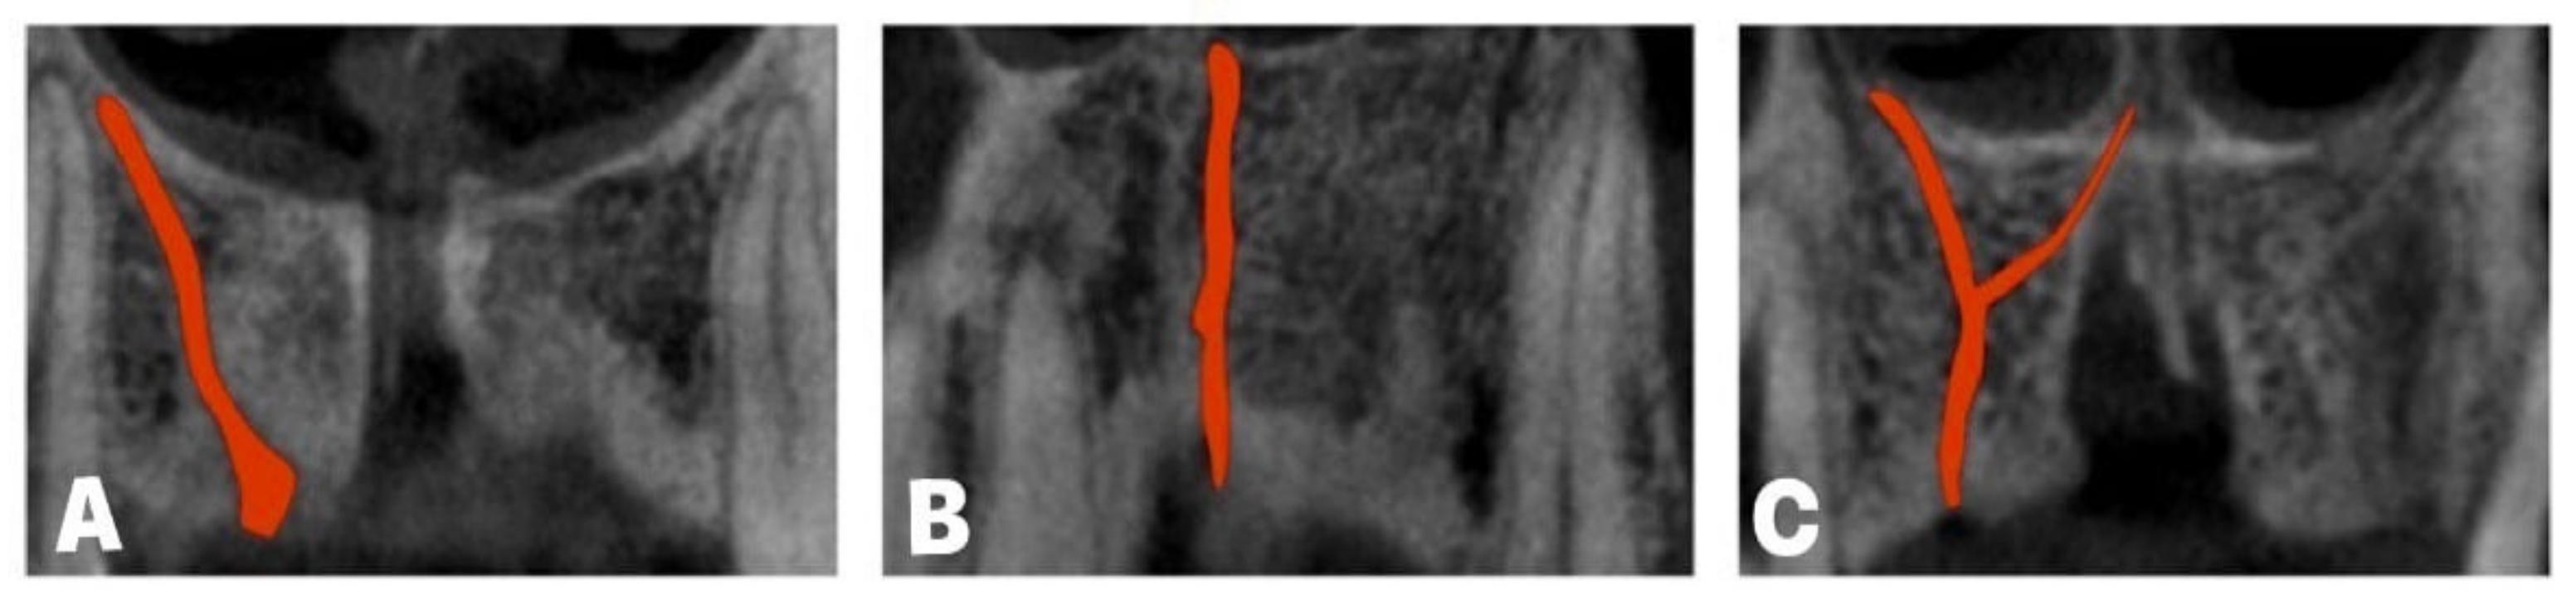

- Vasiljevic, M.; Milanovic, P.; Jovicic, N.; Vasovic, M.; Milovanovic, D.; Vojinovic, R.; Selakovic, D.; Rosic, G. Morphological and Morphometric Characteristics of Anterior Maxilla Accessory Canals and Relationship with Nasopalatine Canal Type-A CBCT Study. Diagnostics 2021, 11, 1510. [Google Scholar] [CrossRef] [PubMed]

- Baena-Caldas, G.; Rengifo-Miranda, H.; Heerera-Rubio, A.; Peckham, X.; Zúñiga, J. Frequency of canalissinuosus and its anatomic variations in cone beam computed tomography images. Int. J. Morphol. 2019, 37, 852–857. [Google Scholar] [CrossRef]

- Machado, V.C.; Chrcanovic, B.R.; Felippe, M.B.; Manhães Júnior, L.R.; de Carvalho, P.S. Assessment of accessory canals of the canalissinuosus: A study of 1000 cone beam computed tomography examinations. Int. J. Oral Maxillofac. Surg. 2016, 45, 1586–1591. [Google Scholar] [CrossRef] [PubMed]

- Von Arx, T.; Lozanoff, S.; Sendi, P.; Bornstein, M.M. Assessment of bone channels other than the nasopalatine canal in the anterior maxilla using limited cone beam computed tomography. Surg. Radiol. Anat. 2013, 35, 783–790. [Google Scholar] [CrossRef] [PubMed]

- Tomrukçu, D.N.; Köse, T.E. Assesment of accessory branches of canalissinuosus on CBCT images. Med. Oral Patol. Oral Cir. Bucal. 2020, 25, e124–e130. [Google Scholar] [CrossRef] [PubMed]

- Wanzeler, A.M.; Marinho, C.G.; Alves Junior, S.M.; Manzi, F.R.; Tuji, F.M. Anatomical study of the canalissinuosus in 100 cone beam computed tomography examinations. Oral Maxillofac. Surg. 2015, 19, 49–53. [Google Scholar] [CrossRef] [PubMed]

- Anatoly, A.; Sedov, Y.; Gvozdikova, E.; Mordanov, O.; Kruchinina, L.; Avanesov, K.; Vinogradova, A.; Golub, S.; Khaydar, D.; Hoang, N.G.; et al. Radiological and Morphometric Features of CanalisSinuosus in Russian Population: Cone-Beam Computed Tomography Study. Int. J. Dent. 2019, 2019, 2453469. [Google Scholar] [CrossRef] [PubMed]

- Manhães Júnior, L.R.; Villaça-Carvalho, M.F.; Moraes, M.E.; Lopes, S.L.; Silva, M.B.; Junqueira, J.L. Location and classification of Canalissinuosus for cone beam computed tomography: Avoiding misdiagnosis. Braz. Oral Res. 2016, 30, e49. [Google Scholar] [CrossRef] [PubMed]

- De Oliveira-Santos, C.; Rubira-Bullen, I.R.; Monteiro, S.A.; León, J.E.; Jacobs, R. Neurovascular anatomical variations in the anterior palate observed on CBCT images. Clin. Oral Implants Res. 2013, 24, 1044–1048. [Google Scholar] [CrossRef] [PubMed]